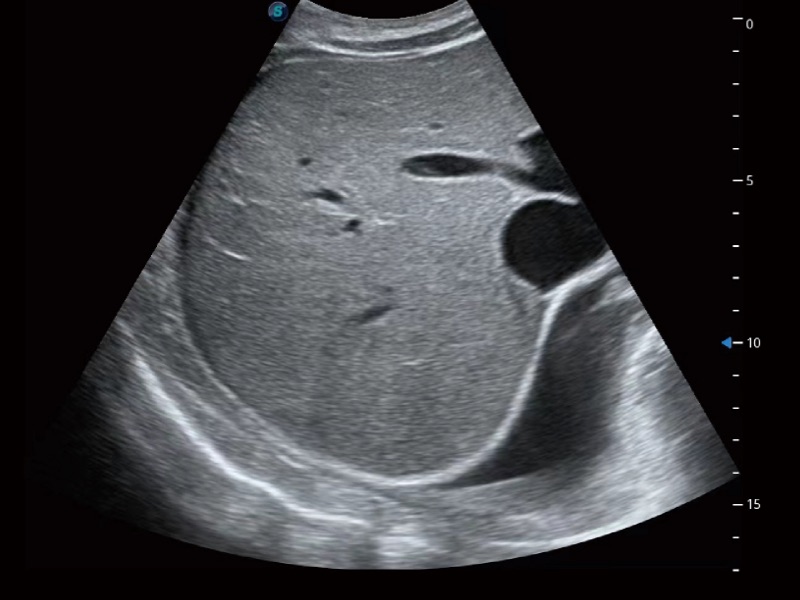

腹部應(yīng)用

超聲檢查得益于實(shí)時(shí)性、經(jīng)濟(jì)性、便捷性,目前廣泛的應(yīng)用于臨床工作中,超聲檢查設(shè)備已成為幫助臨床醫(yī)生輕松地完成診斷工作的好伙伴。P20 Plus集成了一整套包含了腹部、心血管、小器官、婦產(chǎn)科等全面臨床應(yīng)用功能,輕松應(yīng)對(duì)各種臨床問(wèn)題。